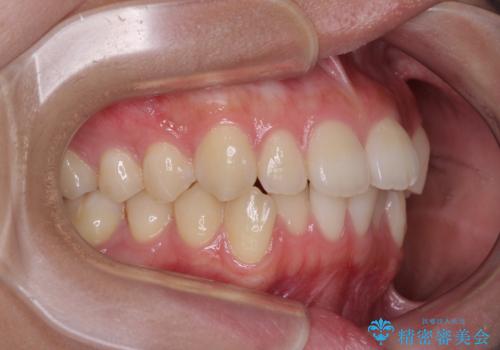

抜歯するほどではないものの、やや口元の突出感が気になっていたので、補助装置により上顎臼歯を後方に移動させることで、突出感改善を図ることとしました。

1年弱の短期間で、望み通りのスッキリとした口元に仕上げることができました。